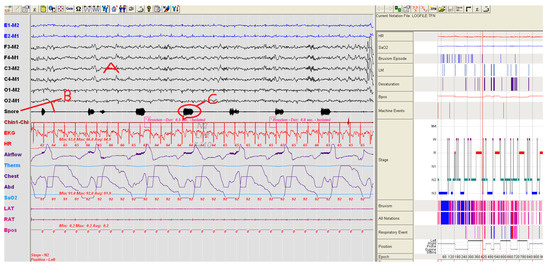

Using the PSG, the number and severity of snoring for each patient were compared. Snoring severity and number of the group using SNORAP were found to be statistically lower (Paired Sample Test, p < 0.05) than when compared to the group not using SNORAP. A volunteer patient from study groups in Figure 7 and Figure 8 was shown a sample PSG recording before and after using SNORAP. 6-channel EEG (A) and snoring trace (B) are given in Figure 7. The high amplitude snoring packets (C) are seen in the snoring trace in Figure 7. Figure 8 shows the PSG recording of the same volunteer patient when the SNORAP was applied to that patient. When his snoring trace in these conditions is reviewed, it is seen that the high amplitude snoring packets are completely removed. No wave of being awake was observed in his sleep EEG.

Figure 7. A patient sample not using SNORAP—high volume snoring sounds are observed in the snore line (A: 6-channel EEG, B: Snoring trace, C: high amplitude snoring packets).

Figure 8. An image of the same patient in Figure 7, while sleeping by using SNORAP and the snoring is completely disappeared (A: 6-channel EEG, B: Snoring trace and it is seen that the high amplitude snoring packets are completely removed).